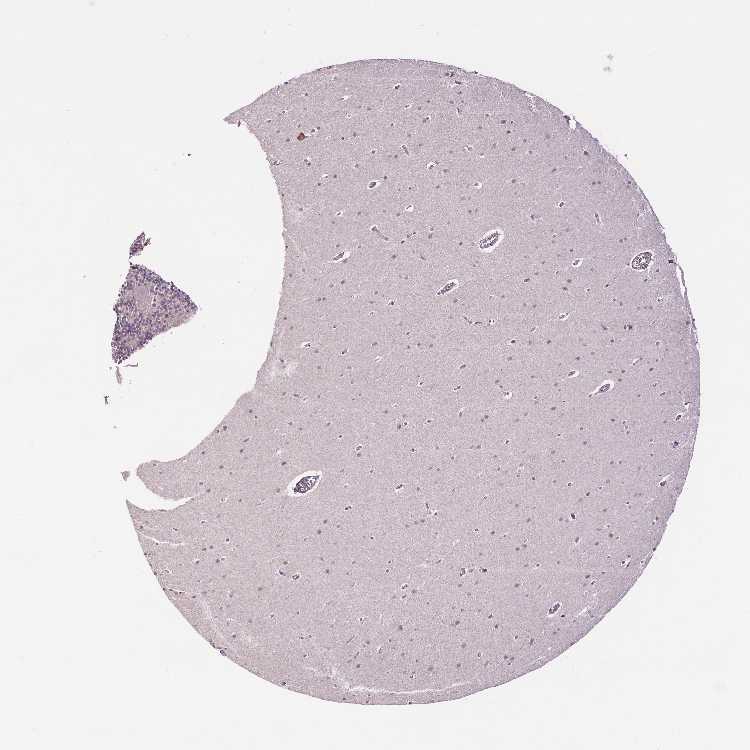

BRAIN CEREBELLUM Show tissue menu

CEREBELLUM - Expression summary

CEREBELLUM - Antibody stainingi

Antibody staining in the annotated cell types in the current human tissue is reported as not detected, low, medium, or high, based on conventional immunohistochemistry profiling in selected tissues. This score is based on the combination of the staining intensity and fraction of stained cells.

Each image is clickable and will lead to virtual microscopy that enables deeper exploration of all samples and also displays staining intensity scores, fraction scores and subcellular localization as well as patient and tissue information for each sample.

Antibody HPA064308Antibody CAB070134

Purkinje cells MediumNot detected

Cells in granular layer Not detectedNot detected

Cells in molecular layer Not detectedNot detected